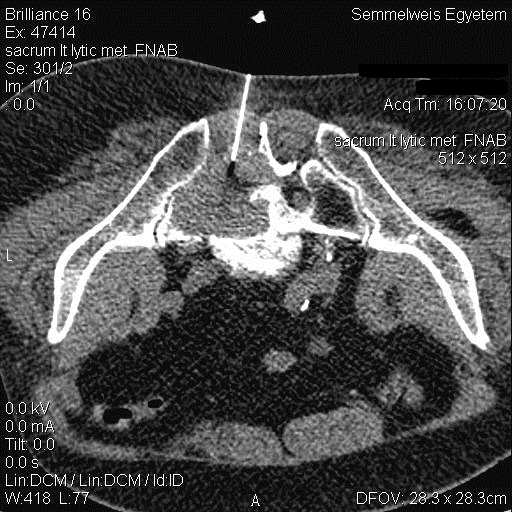

Image

Figure 7. – CT guided sacrum biopsy